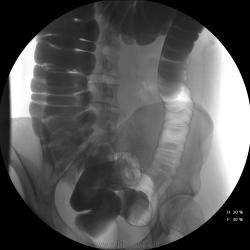

Девушка, 27 лет, жалуется на периодические боли в правой подвздошной области, области паха справа. Во время этого идет нарушение стула - то слабит, то несколько дней не может ходить в туалет, вздутие кишечника. Жалобы несколько лет . Обследованна кем только можно. Хирург посоветовал ирригоскопию. Работа достаточно нервная. До первого случая данных проблем , за неделю, проходила сан лечение в пансионате ( для поднятия общего иммунитета - так говорит), был курс клизм с травами - сама думает, что это не связанно.

В целом -не вижу, к чему придраться, хоть и тонус низковат. Что это? В проекции левого мечеточника. Причем цепочка тенюшек тянется под диафрагму занчительно выше проеции почки?

Цепочка тенюшек - это наша "гордость)" следы от контраста после гистеросальпингоскопии. чтоб вымыть ,надо разбирать стол , а это только с представителем сименса. вот так.) а правые отделы толстой кишки на расширены? я кроме лополнительной петли сигмы сам ничего не вижу. несколько настораживает некоторое расширение правых отделов кишки- может за счет запоров, которые случаются у девушки? не хочется что то пропустить.

А, чем вызвана неоднородность контрастирования слепой и частично восходящего отдела?

Тугого контрастирования слепой не достигнуто. Должны быть причины.

Слепая кишка в конце исследования, несмотря на её содержимое, заполнилась прилично. А вот гаустрация сигмовидной кишки не сглажена?